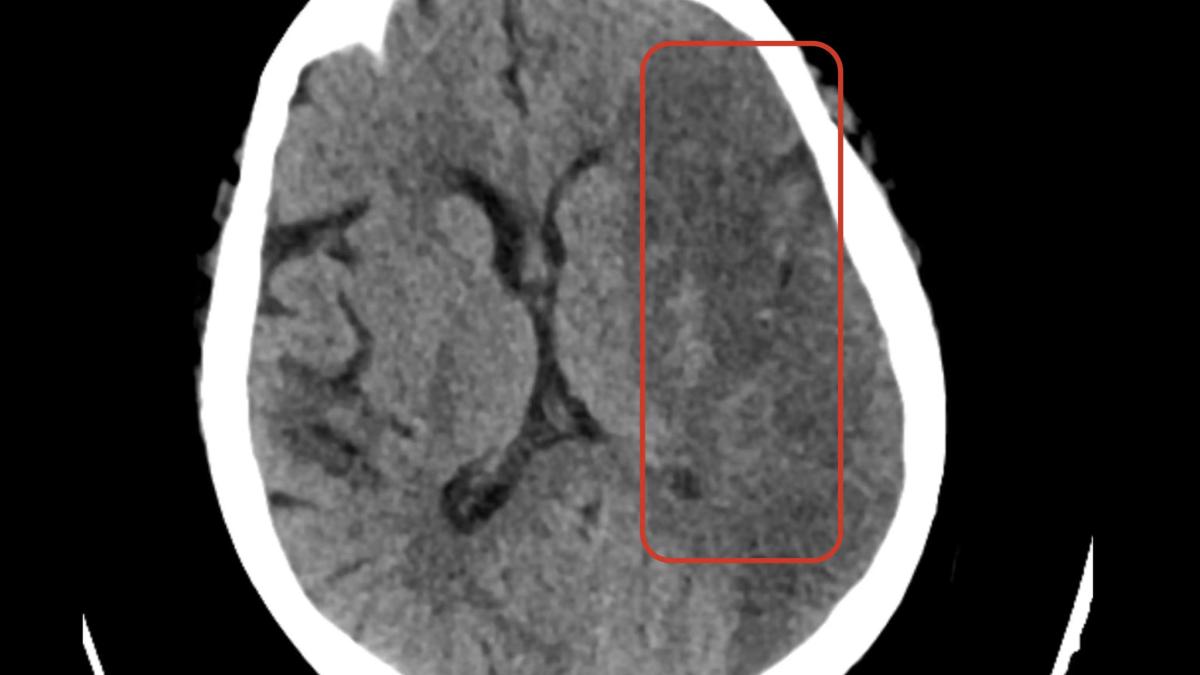

Cazul 2: Infarctul cerebral "ascuns"

Femeie, 71 ani. Simptome neurologice ușoare, intermitente. CT-ul cerebral pare normal la prima vedere – modificările ischemice acute sunt adesea subtile în primele ore.

CAREBOT identifică zonă de hipodensitate în teritoriul arterei cerebrale medii – semn precoce de infarct. Confirmarea salvează pacientul de la un AVC masiv catastrofal câteva ore mai târziu.